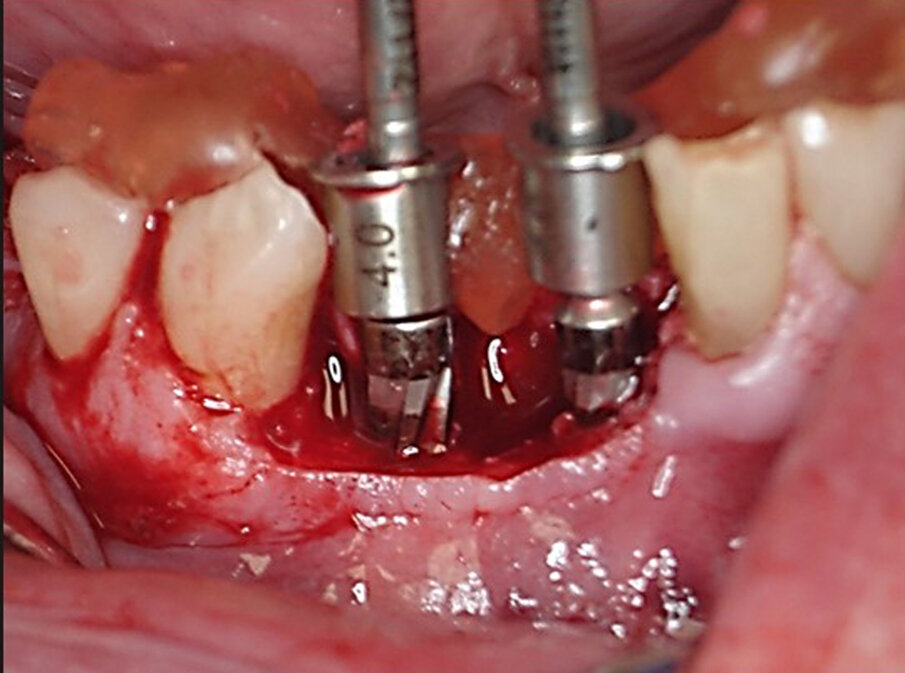

The surgical stent was soaked in povidone-iodine prior to use surgically. Chlorhexidine may be used as an alternative liquid to disinfect the guide. Local anaesthetic was administered, and the surgical guide verified for fit and stability intra-orally (Figs. 12a & b). A crestal incision was made with a scalpel, and a full-thickness flap was reflected to expose the crest. The Guide Right surgical guide with 4 mm guide sleeves was inserted. The osteotomies were initiated with a 2.2 mm drill in a 2.3 mm insert and completed with Densah osseodensification burs (Versah), starting at 2.5 mm and continuing to 3.5 mm in diameter to a depth of 11.5 mm at both sites through the surgical guide (Fig. 13). A 3.5 × 11.5 mm implant was placed into the central incisor site and a 4.0 × 11.5 mm implant was inserted into the canine site (AnyRidge, MegaGen). A post-insertion radiograph was taken (Fig. 14a). Cover screws were placed on both implants, and the flap was secured with sutures.